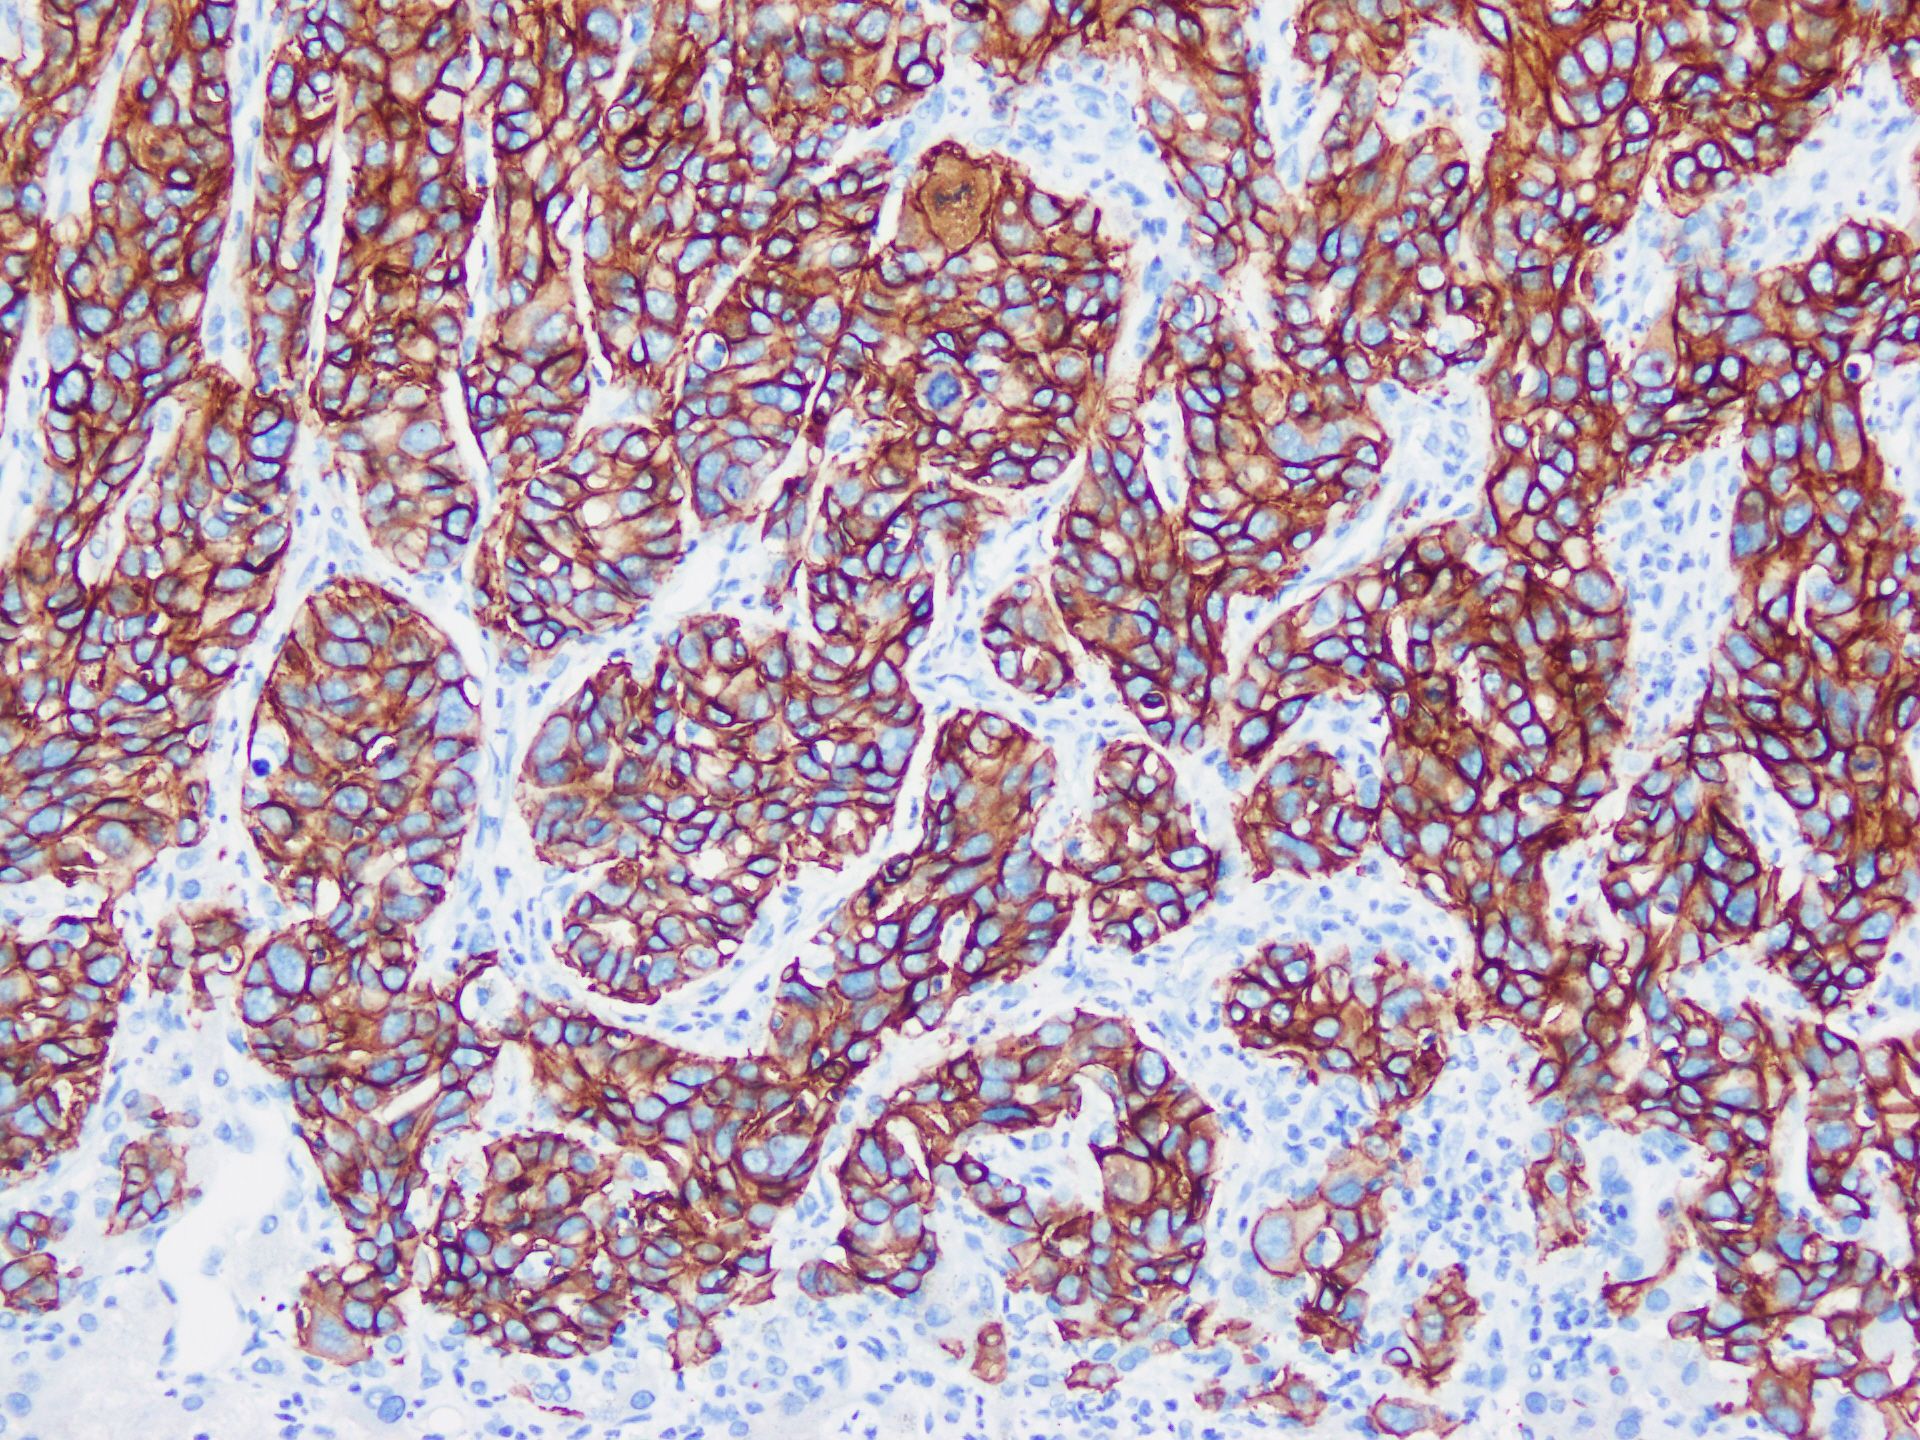

3.3 HER2 overexpression/amplification

The HER/erythroblastic leukemia viral oncogene homolog (ERBB) family proteins are type I transmembrane growth factor receptors that function to activate intracellular signaling pathways in response to extracellular signals. The members of HER family of kinases were shown to form both homodimers and heterodimers with each other, resulting in the activation of crucial cell signaling pathways, including the phosphatidylinositol 3 kinase (PI3K)/protein kinase B (AKT) pathway. HER3 interacts directly with PI3K, and HER2 indirectly activates this pathway through its interaction with HER3. The overexpression/amplification of HER2 is implicated in multiple cancers (146). HER2 detection can be achieved through immunohistochemistry, FISH, and NGS. HER2 immunohistochemistry has been widely employed in various cancer types such as breast cancer, gastrointestinal adenocarcinoma, and bladder cancer, and their standardized approaches are highly thorough. The commonly employed clone of HER2 includes 4B5, HercepTest, CB11, and so on. For biliary tract cancer, the high-grade evidence of approved HER2-targeted drugs is based on four clinical studies. The first one is the MyPathway study, where Pertuzumab combined with Trastuzumab was performed to treat metastatic biliary tract cancer patients with immunohistochemistry 3+ HER2, HER2 amplification indicated by FISH or chromogenic in situ hybridization (HER2:CEP17 ratio > 2.0, or HER2 copy number > 6.0), or HER2 amplification detected by NGS (HER2 copy number gain) (147). The second is the SGNTUC-019 study, in which Tucatinib and Trastuzumab were used to treat metastatic biliary tract cancer patients with the same inclusion criteria as the MyPathway study (148). The third is Trastuzumab Deruxtecan for the treatment of advanced solid tumor patients with immunohistochemistry 3+ HER2 (149). The fourth study is HERIZON-BTC-01 which validated that Zanidatamab could improve the prognosis of the unresectable, locally advanced or metastatic biliary tract cancer patients with HER2 2+ and 3+, especially for the latter population (150). Regarding the percentage of positive cases of HER2 expression in iCCA, a meta-analysis including 40 studies showed that when the moderate/strong positive expression of HER2 was defined as positive, the percentage of positive cases of HER2 expression in iCCA was 4.8% (151). Another study incorporating 110 iCCAs suggested that when evaluated based on the guideline from the College of American Pathologists, American Society for Clinical Pathology, and the American Society of Clinical Oncology for gastroesophageal adenocarcinoma (152), the detection percentage of 2+ and 3+ HER2 expression in iCCA was 3.7% (153). One more study including 27 cases of iCCA indicated that when HER2 scoring was performed under the 2018 version of the American Society of Clinical Oncology/College of American Pathologists Clinical Practice Guideline (154), the detection percentage of 2+ and 3+ HER2 expression in iCCAs was also 3.7% (155). In terms of prognosis, a meta-analysis including 31 studies revealed that the overall survival of biliary tract cancer patients with HER2 overexpression was poorer, but when specified to the patients of iCCA, the conclusion still need further verification (156). Currently, there is no evidence for an independent HER2 immunohistochemical interpretation standard for iCCA, mainly referring to the methods of gastrointestinal adenocarcinoma and breast cancer. Considering that clear clinical evidence has been obtained through these methods, it is feasible from an empirical perspective (Figure 7). Additionally, although the majority of HER2 alterations are gene overexpression or amplification, activating missense mutations have also been proven to be an important subset of HER2 alterations, which cannot be detected by immunohistochemistry.

Figure 7. iCCA with heterogeneous HER2 status. (a) HER2 0; (b) HER2 1+; (c) HER2 2+; (d) HER2 3+; (e) FISH demonstrates HER2 amplification.